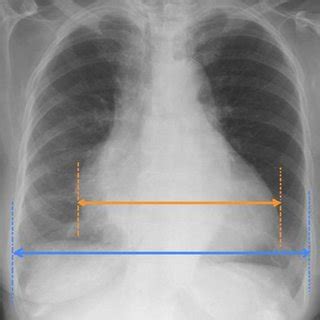

What Can a Mesothelioma Chest X Ray Reveal?

While a standard chest X-ray can't give a definitive diagnosis, it can show abnormalities that are consistent with mesothelioma. Radiologists look for specific patterns and changes that might indicate the presence of this aggressive cancer. These signs are crucial for guiding the next steps in diagnosis.

Some of the common findings on a Mesothelioma Chest X Ray that might raise suspicion include:

- Pleural Thickening: This is one of the most common signs, where the lining of the lungs (pleura) appears thicker than normal.

- Pleural Plaques: Calcified areas on the pleura, often a sign of past asbestos exposure, though not cancerous themselves, they indicate risk.

- Pleural Effusion: An accumulation of fluid between the layers of the pleura, which can be a symptom of mesothelioma.

- Lung Volume Loss: A decrease in the size or volume of a lung, often due to significant pleural thickening.